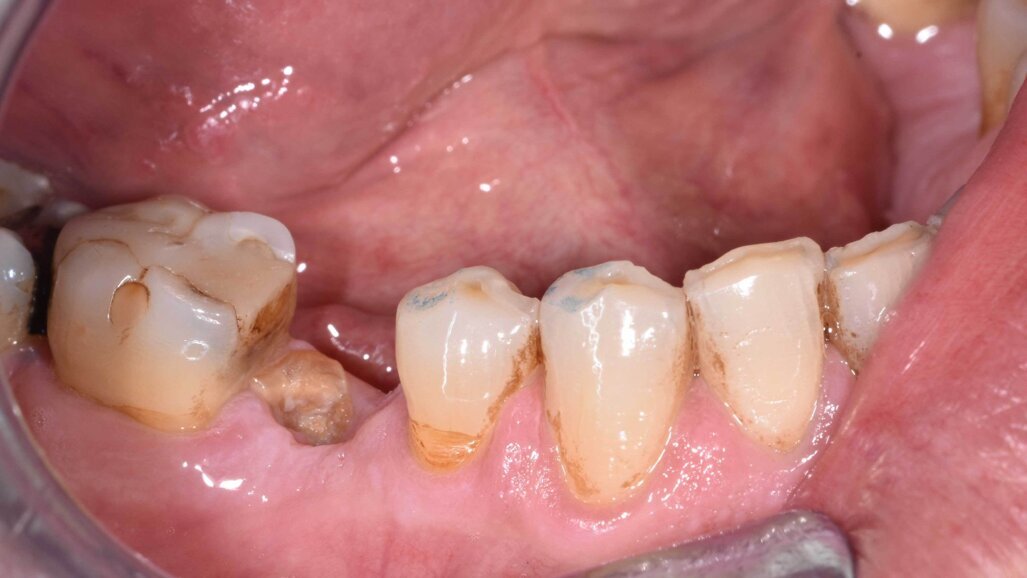

G. I. paziente di anni 50, si presenta alla nostra osservazione con una frattura longitudinale della radice dell’elemento 4.5 dovuta a infiltrazione cariosa della vecchia corona protesica. Questa situazione ha provocato nell’osso alveolare del paziente una grossa lesione che è andata ad interessare anche la corticale vestibolare. Per poter sostituire la radice con un impianto sarebbe necessario un intervento di chirurgia ossea rigenerativa ma un’alternativa meno invasiva è la rigenerazione del tessuto osseo ottenuta tramite l’estrusione forzata dell’elemento che rigenera osso durante la sua lenta migrazione grazie al legamento parodontale. In accordo con il paziente, dopo opportuna spiegazione dei benefici e dei tempi dell’approccio con estrusione ortodontica, si decide di procedere con questo iter evitando così l’intervento di rigenerativa.

In questo caso clinico la difficoltà consisteva nel fatto che si è resa necessaria l’estrazione della metà mesiale della radice fratturata e quindi nel far compiere al frammento radicolare rimasto un movimento diagonale per mezzo del quale la porzione distale rimasta con il legamento parodontale avrebbe permesso una corretta rigenerazione tissutale ossea come indicato in rosso nell’immagine radiografica.

L’estrusione completa del frammento ha richiesto un tempo di 6 mesi, durante i quali è stata modificata più volte l’inclinazione della molla per evitare che il movimento diventasse ortogonale al segmento e mantenere la traiettoria prevista. Così facendo, è stato possibile rigenerare naturalmente l’intero alveolo e inserire, dopo 3 mesi di ulteriore maturazione del tessuto, in un contesto osseo ideale e perfettamente rigenerato un impianto Syra (Sweden & Martina) di diametro 4.25 mm e lungo 11 mm.